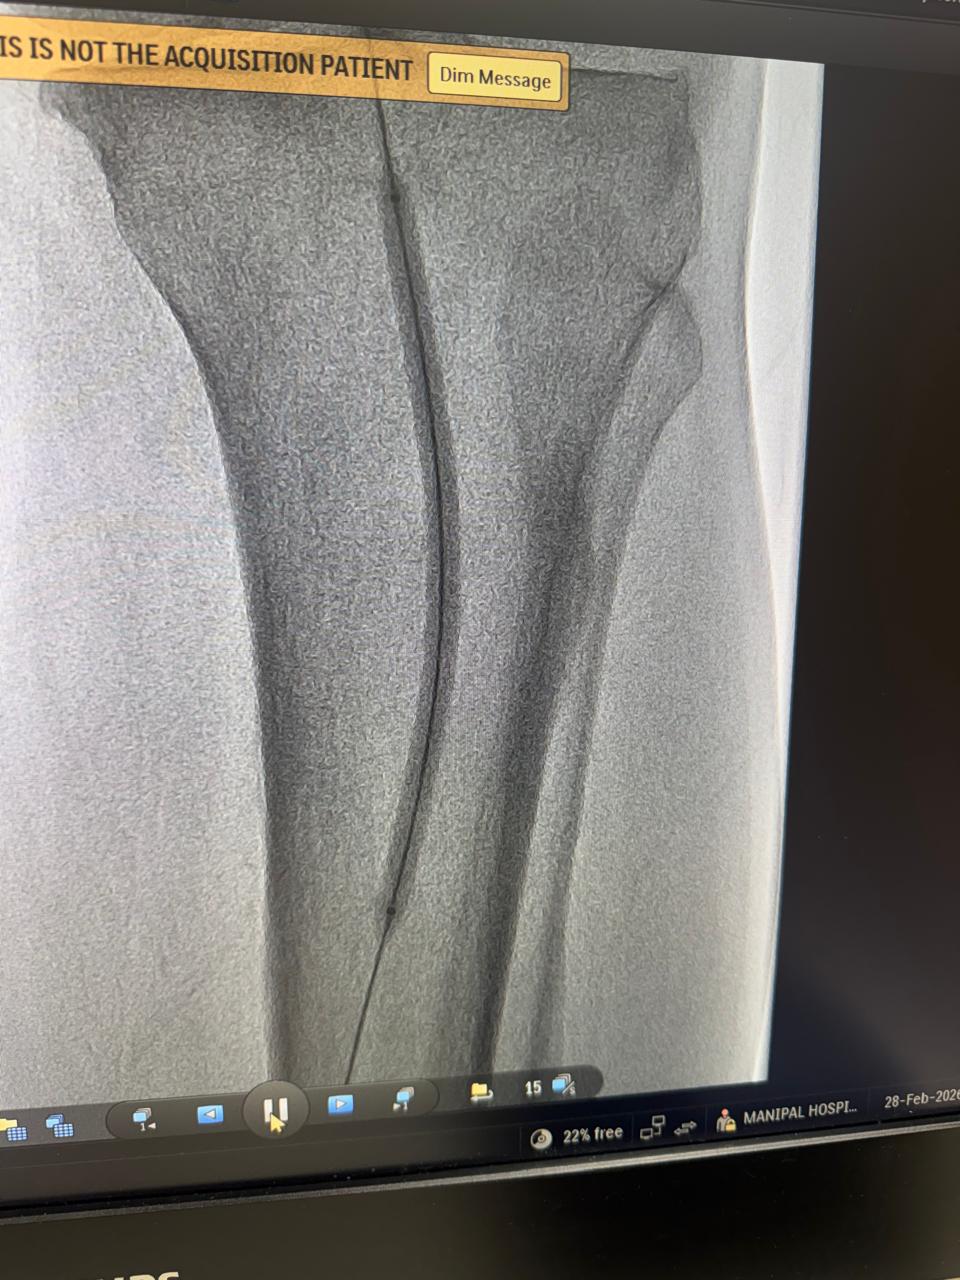

60 year male patient with uncontroll diabetes , forefoot gangrene and below knee vessel disease,below knee angioplasty and debridement done ,also regular dressing and diabetes uncontrol,wound ready to skin graft